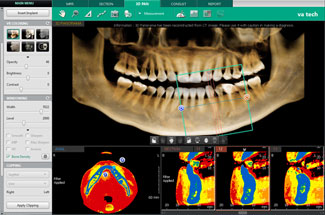

Программный продукт также имеет ряд преимуществ при анализе проделанной работы. Вся информация архивируется, в том числе возможно внесение различных фото после проведения эстетического лечения. Требования пациентов к итогам лечения зависят от их восприятия трудностей в полости рта, однако часто это только частично отражает истинную клиническую ситуацию. Многие пациенты получают информацию из изданий или бытовых советов знакомых. В большинстве случаев, они имеют весьма относительное представление о реальных особенностях этой процедуры, сложностях ее проведения и возможных в дальнейшем проблемах. Другие могут получить большой объем информации через интернет, но не могут упорядочить ее, или то, что они узнали, совершенно не подходит для их ситуации. Поэтому в задачи стоматологов входит убедиться, что пациент понимает суть своего состояния, возможности лечения, а также оказать ему помощь в выборе правильного решения. В этой связи приложение оснащено 200 мультимедийными роликами для создания комфортных условий консультаций пациентов, где в доступной форме отражена планируемая процедура вмешательства. Показательность информации, наряду с комментариями профессионала приводят к сотрудничеству пациентов для точного понимания своего клинического случая. Программное средство Ez3D-i V4, рассчитанное на работу с трехпроекционным объектом исследования по праву является передовым на рынке диагностической инженерии. При подготовке к хирургическому этапу имплантации программное обеспечение Ez3D-i V4 дает огромный спектр опций. Построение трех проекций, с возможностями переориентации осей, с точным измерением габаритов интересующей области, маркировки хода нижнечелюстного канала, в том числе, и, на кросс-секционном изображении (Рис.5), а также диагностика дополнительных ответвлений (добавочные каналы Робинзона)(Рис.6), визуализация верхнечелюстных пазух, виртуальный позиционер имплантатов (Рис.7), позволяющий спрогнозировать оперативное вмешательство с помощью любой фирмы - производителя имплантационных систем, измерение плотности костной ткани в зоне планируемой имплантации по шкале Хаунсфилда HU (Рис.8). Виртуальная реальность представлена в масштабе 1:1, что дает 100% информативности, а значит и 100% эффективности планируемого лечения. После того как программа произвела инсталляцию имплантата, хирург в приложении моделирует его ангуляцию, инклинацию и погружение, учитывая все анатомические факторы риска. Функции "Удалить или Скрыть" имплантат, используют при замене длины и диаметра имплантата или выборе иной марки производителя.

Рис.7 Виртуальный планировщик имплантатов П/О Ez3D-i V4

Рис.8 Определение плотности костной ткани в зоне планируемой имплантации с помощью виртуального дентального позиционера П/О Ez3D-i V4